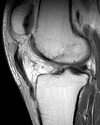

Figure 1 is the MRI scan of a 15-year-old boy who has had knee pain with running for 5 months. What is the most appropriate treatment?

Arthroscopic or open reduction and internal fixation ## Footnote OCD is an acquired lesion of the subchondral bone. Patients with OCD initially report nonspecific pain and variable amounts of swelling. **Initial radiographs help identify the lesion and establish the status of the physes**. An MRI scan is useful for assessing the potential for the lesion to heal with nonsurgical treatment. **Nonsurgical treatment is appropriate for small, stable lesions in patients with open physes and focuses on activity restriction for 3 to 9 months**. Surgical treatment is necessary for unstable or detached lesions. Stable lesions with intact articular cartilage can be treated with subchondral drilling to stimulate vascular ingrowth, with radiographic healing at an average of 4.4 months. Fixation is indicated for unstable or hinged lesions, and stabilization of the fragment can be achieved using a variety of implants through an arthroscopic or open approach. The fragment should be salvaged and the normal articular surface restored whenever possible.